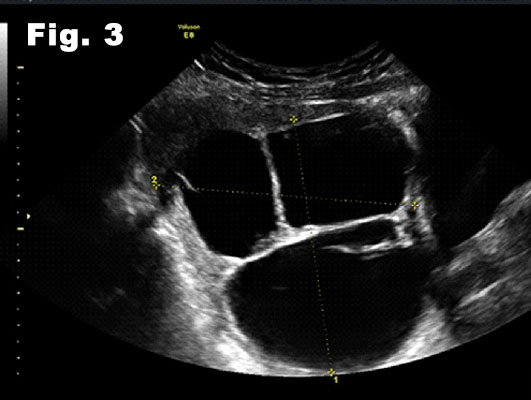

Both ovaries were morphologically normal. All pelvic organs were mobile and the patient did not complain about pain during the examination. Trans-abdominal scan confirmed the diagnosis of the transvaginal scan (fig 3, 4). All these regular, rounded and avascular masses detected on ultrasound were suggestive of benign lesions. We offered to the patient a transvaginal needle biopsy to confirm the diagnosis. Cytology of aspirated fluid was negative for malignancy and a follow up scan in six months' time was recommended.

Figure 3:Trans-abdominal scan, longitudinal view. Dimensions of the multilocular lesion, measuring 80x80mm.

![Cystic fibroids</br> [Feb 2017]](http://s834315022.websitehome.co.uk/wp-content/uploads/2020/11/cotm-feb2017-fig3.jpg)